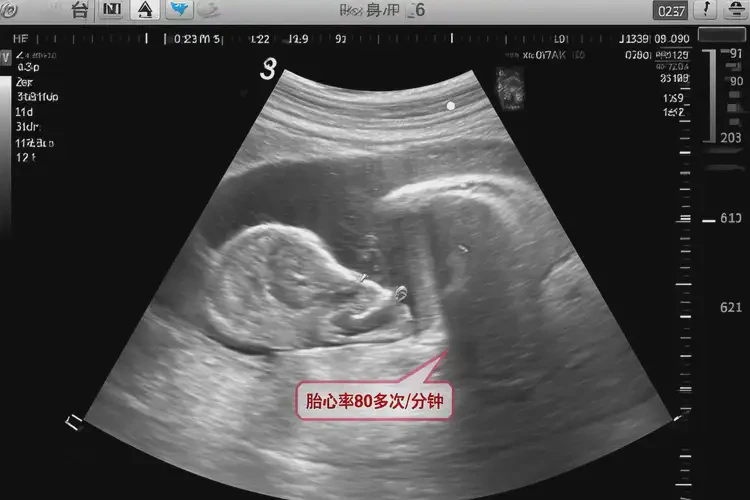

孕11周3天胎心率80多有危險(xiǎn)嗎

胎心率是評(píng)估胎兒健康狀況的重要指標(biāo)之一。在孕11周3天時(shí),正常的胎心率范圍通常在120-160次/分鐘。如果胎心率低于120次/分鐘,可能提示胎兒存在缺氧或其他健康問題。胎心率80多在孕11周3天可能存在風(fēng)險(xiǎn),需要引起重視。

孕11周3天胎心率80多有危險(xiǎn)嗎(圖1)

通過上述表格,我們可以更直觀地了解不同胎心率范圍所對(duì)應(yīng)的風(fēng)險(xiǎn)評(píng)估和建議措施。在孕11周3天時(shí),胎心率80多屬于中度異常范圍,需要立即進(jìn)行進(jìn)一步評(píng)估和治療。

胎心率是評(píng)估胎兒健康狀況的重要指標(biāo)之一。在孕11周3天時(shí),胎心率80多可能存在風(fēng)險(xiǎn),需要引起重視。如果發(fā)現(xiàn)胎心率異常,應(yīng)及時(shí)就醫(yī)進(jìn)行進(jìn)一步評(píng)估和治療,以確保胎兒的健康發(fā)育。